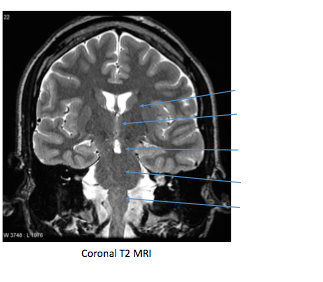

Label image shown

Top to bottom R to L:

Label the image shown